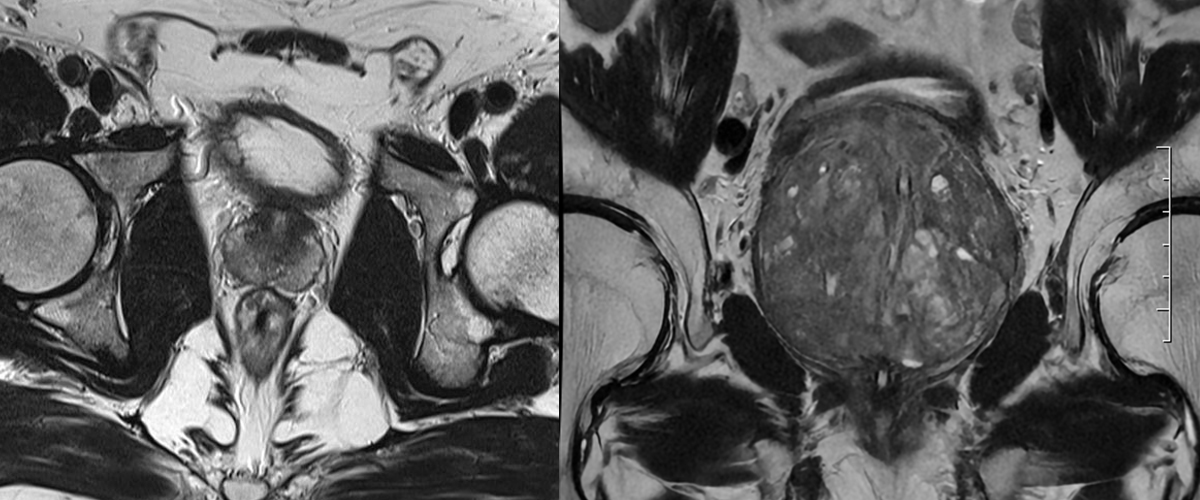

Prostat MR , prostat bezi ve çevresindeki yapıların detaylı olarak görüntülenmesini sağlayan, non-invaziv bir tıbbi görüntüleme yöntemidir. Prostat kanseri başta olmak üzere, prostatla ilgili diğer hastalıkların teşhisinde ve takibinde kullanılır. Radyasyon içermemesi ve yumuşak dokuların ayrıntılı bir şekilde görüntülenmesine olanak sağlaması nedeniyle oldukça güvenilir bir yöntemdir.

• Detaylı Görüntüleme: Prostat bezinin anatomik yapısını ve hastalıkların yerleşimini ayrıntılı bir şekilde gösterir.

• Multiparametrik MR (mpMRI): Prostat MR genellikle "multiparametrik MR" olarak yapılır. Bu yöntem anatomik, fonksiyonel ve moleküler düzeyde bilgiler sunar.

• Kanserli dokunun yerini, boyutunu ve çevreye yayılımını değerlendirir.

• Kanserin Ayırt Edilmesi: Kanserli dokuların prostatın diğer bölümlerinden ayrımını yapar.